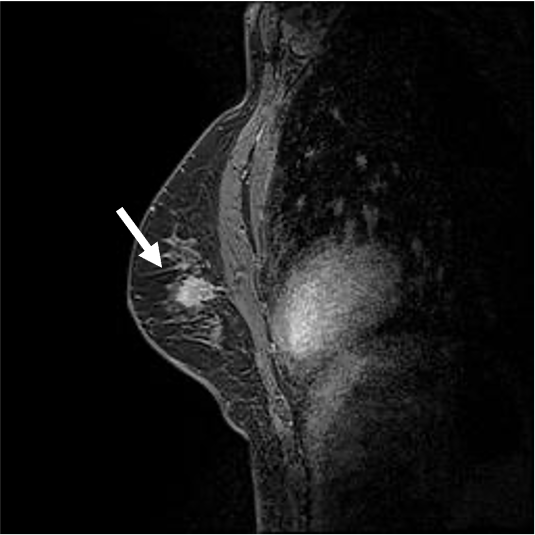

検診で指摘された左乳房腫瘤に対してMRI精査を行った症例である。BPEはminimalで病変の同定は容易であった。拡散強調像では明瞭な高信号あり、ADCの低下を認め、細胞密度は高いと考えられた。造影MRIにて辺縁不整な形状である事が明瞭となり、ダイナミック早期相では辺縁優位に造影効果を認め、TIC( Time intensity curve)ではFast-plateauパターンを示し乳癌を疑った。

cT1cN0M0の診断となり乳房温存術、術後放射線療法が施行された。

病理では硬性型の浸潤性乳管癌と診断された。

当該疾患の診断における造影MRIの役割

病変の辺縁の性状、境界、内部の造影パターンの把握にダイナミック造影MRIが必須である。今回の症例は単発病変であったが、多発病変でBPE(background parenchymal enhancement)がある症例では病変部と非病変部の区別に注意が必要である。